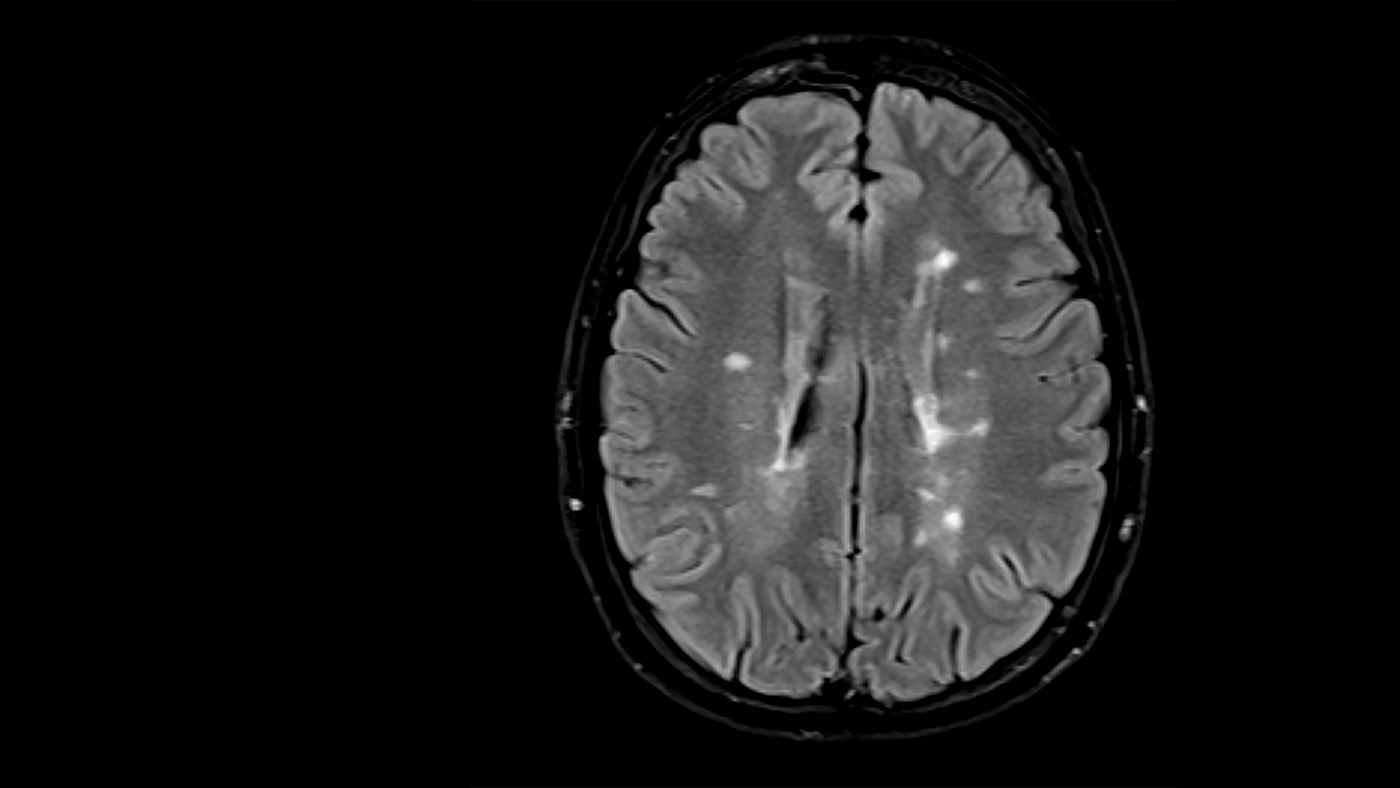

The acquisition of raw data for medical images is often time consuming or harmful to patients. Algorithms and techniques that allow us to reconstruct images from datasets that are under-sampled or corrupted by artifacts can enable an improved patient experience and reduce costs. At Microsoft we are engaged in the development of machine learning models that facilitate accelerated imaging. We have enhanced the InnerEye (opens in new tab) toolkit to support training of reconstruction models. Specifically, we are providing dedicated tooling to enable the use of the FastMRI (opens in new tab) dataset and existing model architectures. This includes tooling for managing the large MRI raw datasets needed for training the models. We have also published clinical annotations (opens in new tab) that enable evaluation of new models in the context of pathology.